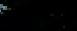

VETERINARY RADIOGRAPHIC REPORT

HORSE: "XXXXXXXX"

DATES OF EXAMINATION: 26TH AUG, 21ST OCT 21 & 17TH NOV '21

PLACE: XXXXXXXXXX FARM

XXXXXXX's left and right front feet were radiographed on 26th Aug, 21st Oct (8 weeks) and again on the 17th Nov '21(12 weeks).

RADIOGRAPHS:

26.08.21: Right Front: Large P3 solar margin fracture evident on medial toe 32.6mm x 4.1mm with approximately 1.4mm separation from parent bone as below left image.

21.10.21: Right Front: Fine residual 4.2mm fracture still evident, approximately 90% resolution

17.11.21: Right Front: Fracture fully resolved

RECOMMENDATIONS:

Radiographic results as of the 17th Nov '21 show total resolution of the original fracture.

XXXXXXX was reshod today utilising off an alloy shoe with a toe clip - inner circumference seated out to avoid any sole pressure.

The horse can return to training. Please do not hesitate to contact me if you have any further queries

COMMENTS:

Solar margin Type IV fractures of this magnitude have well-documented internationally published healing rates of 7 - 12 months. Full resolution of these fractures is rare as most often the fracture fragments are resorbed.

Full resolution in a 3 month period was not anticipated.

The horse was on Bone Gold 3 x scoops fed once per day for this period.